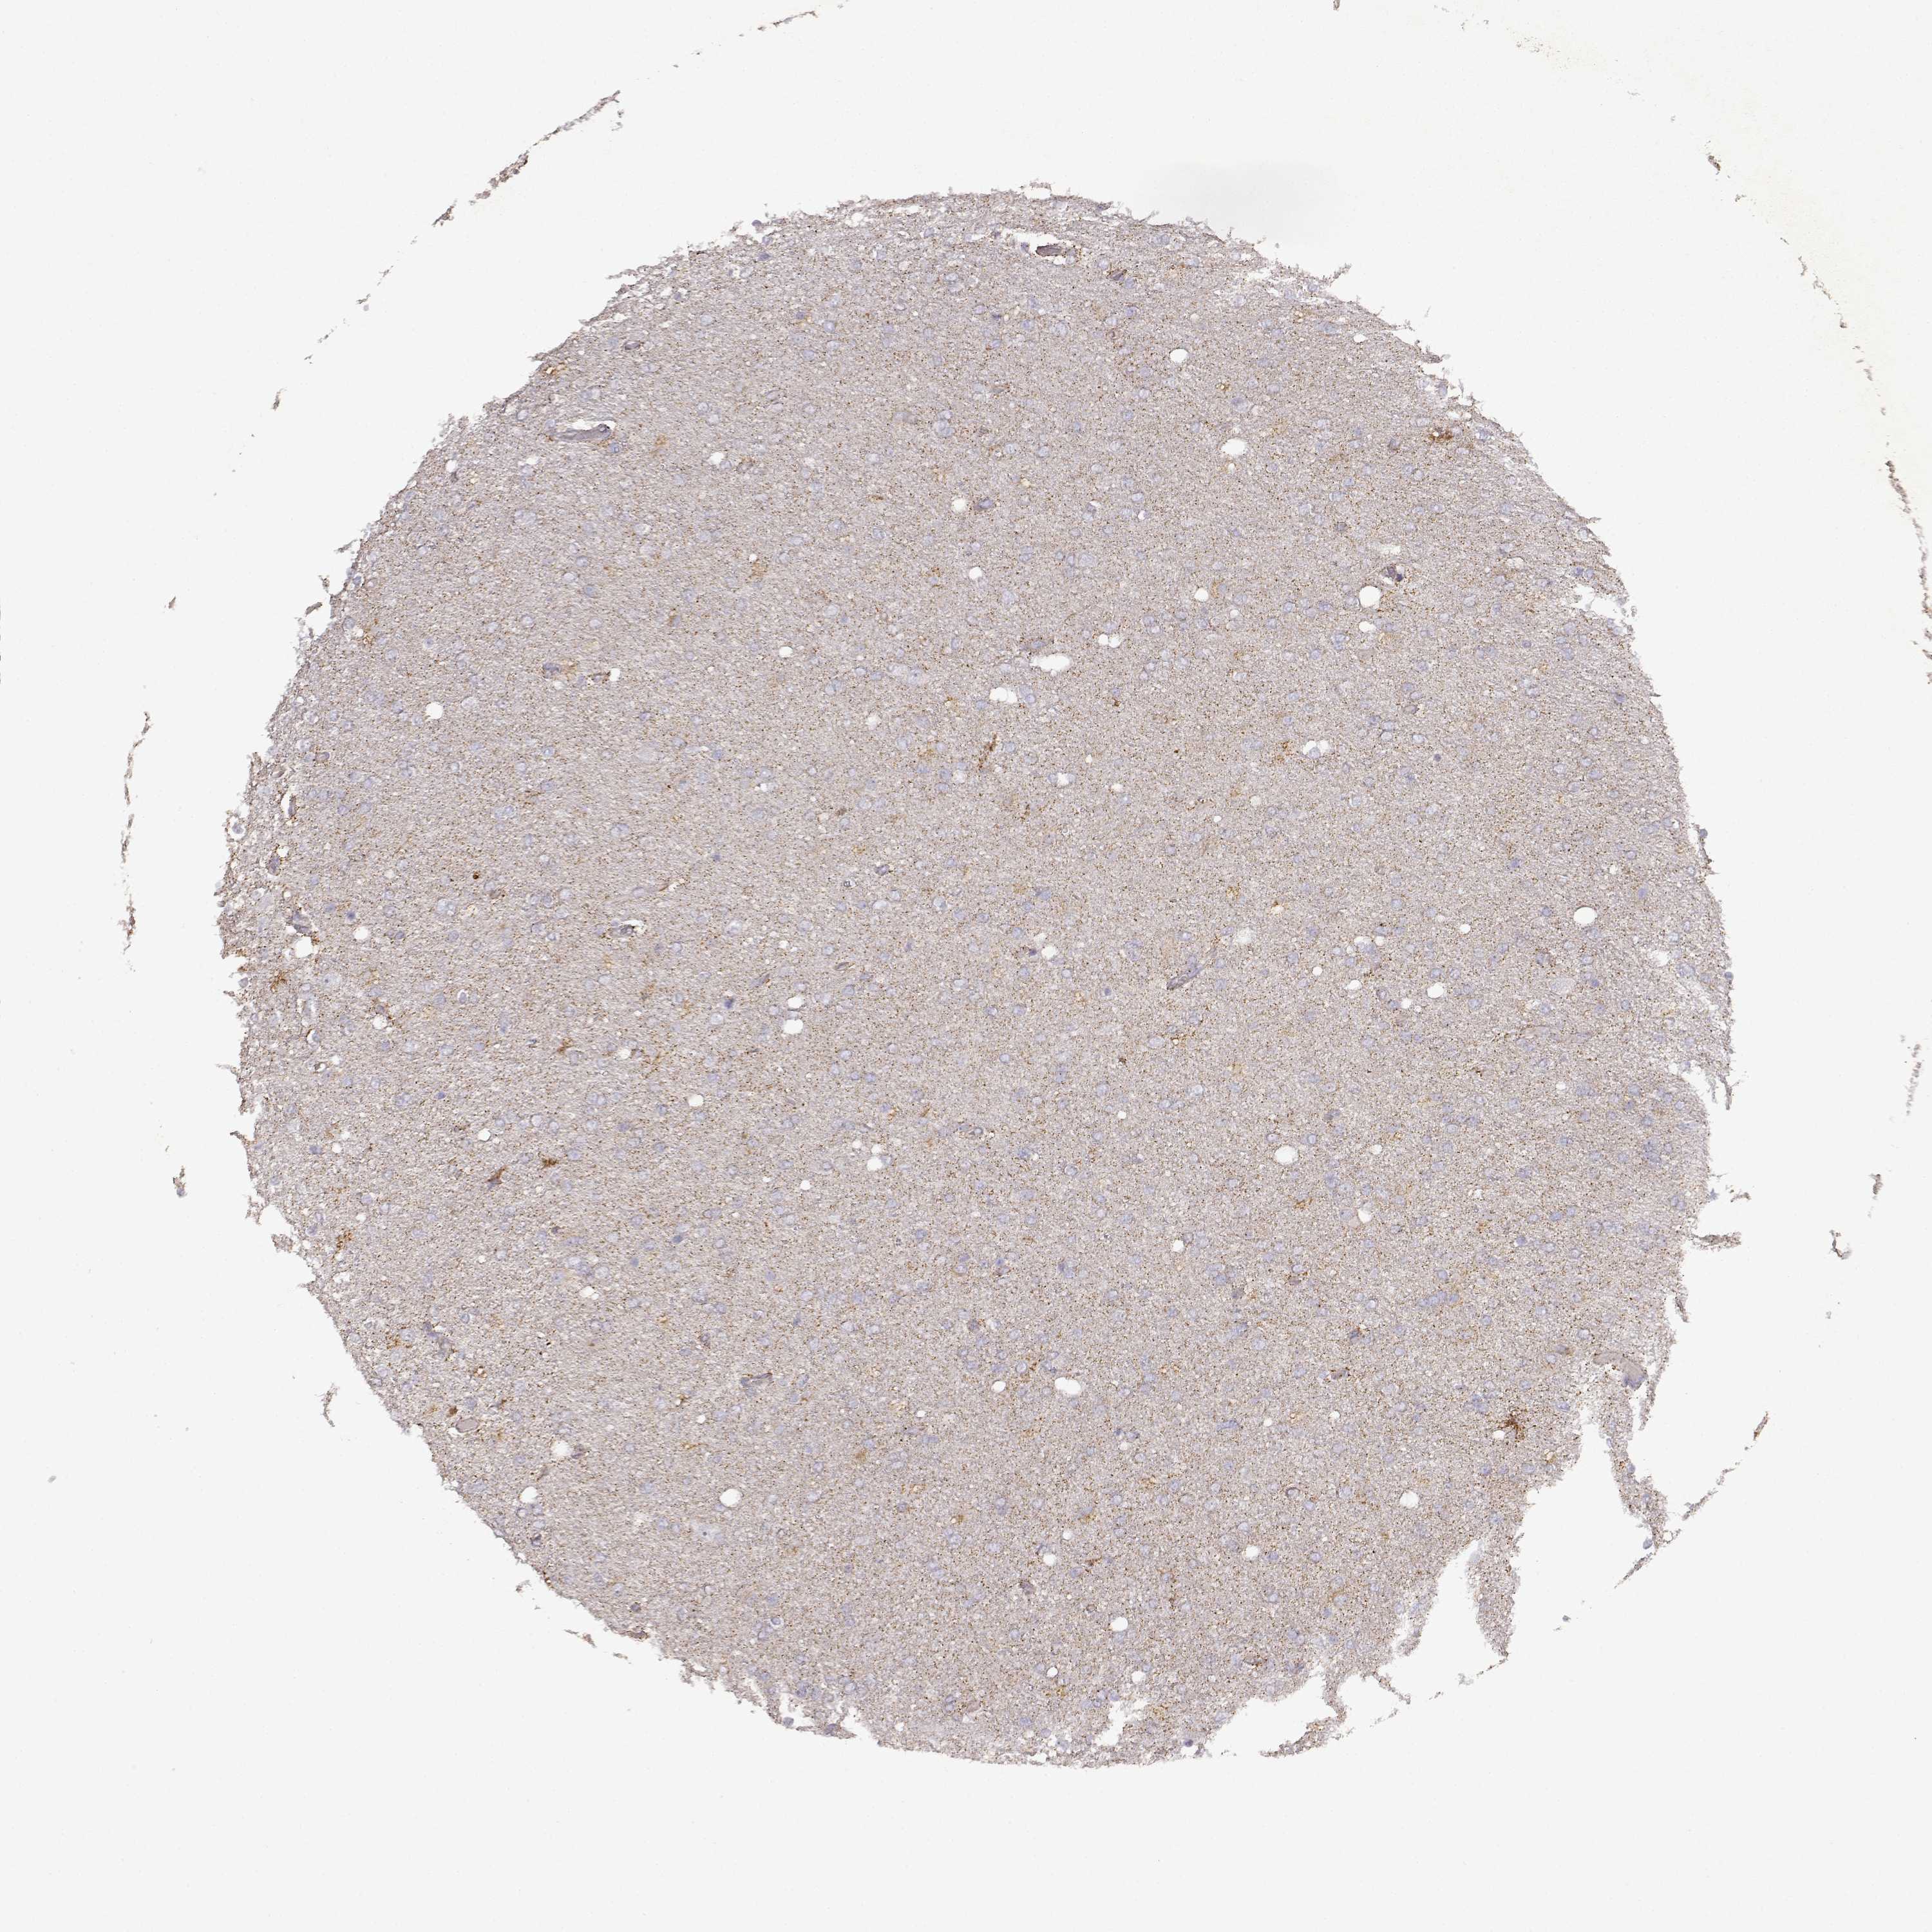

GLIOMA - Protein expressioni

A mouse-over function shows sample information and annotation data. Click on an image to view it in a full screen mode. Samples can be filtered based on level of antibody staining by selecting one or several of the following categories: high, medium, low and not detected. The assay and annotation is described here.

Note that samples used for immunohistochemistry by the Human Protein Atlas do not correspond to samples in the TCGA dataset.

Antibody stainingi

Antibody staining in the annotated cell types in the current human tissue is reported as not detected, low, medium, or high, based on conventional immunohistochemistry profiling in selected tissues. This score is based on the combination of the staining intensity and fraction of stained cells.

Each image is clickable and will lead to virtual microscopy that enables deeper exploration of all samples and also displays staining intensity scores, fraction scores and subcellular localization as well as patient and tissue information for each sample.

Antibody HPA017742

Staining

High

Medium

Low

Not detected

Intensity

Strong

Moderate

Weak

Negative

Quantity

>75%

75%-25%

<25%

None

Location

Nuclear

Cytoplasmic/membranous

Cytoplasmic/membranous,nuclear

Glioma, malignant, Low grade

Glioma, malignant, High grade